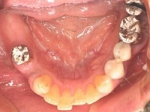

片側2歯欠損片側2歯欠損片側2歯欠損 主訴-入れ歯を使ってみたが違和感強くてダメ。固定のものにしたい。術前下顎口腔内(鏡像) 二次オペ時(鏡像)二次オペ時(鏡像)二次オペ時(鏡像) 術後術後術後、左下奥2本インプラント(鏡像) 術後(レントゲン)術後(レントゲン)術後(レントゲン)、左下奥2本インプラント

両側5歯症例

両側5歯症例両側5歯症例両側5歯症例 主訴-義歯のバネが壊れて手前の歯が痛んできた。 術前(旧義歯装着、鏡像) 術前(下顎粘膜面、鏡像)術前(下顎粘膜面、鏡像)術前(下顎粘膜面、鏡像) 術前レントゲン術前レントゲン術前レントゲン 術前口腔内(正面観)術前口腔内(正面観)術前口腔内(正面観)

術後(鏡像)術後(鏡像)術後(鏡像) 術後口腔内(正面観)術後口腔内(正面観)術後口腔内(正面観)もう入れ歯は要らなくなりました。 術後レントゲン術後レントゲン術後レントゲン